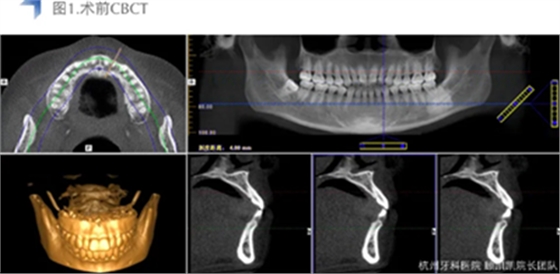

接诊后口内检查12近中邻面较大面积龋齿,探不适,叩无不适,冷热测试同时对照牙及临牙,BOP+,扪诊(-),未有异常松动度。术前CBCT检查如下图,未见明显根尖周透射影。